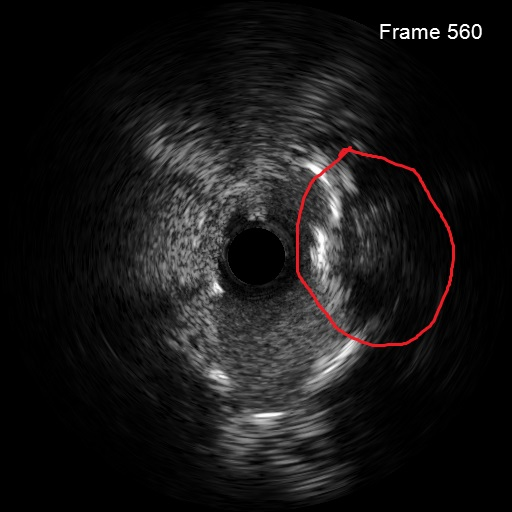

考虑到患者钙化严重且弥漫,为精准化钙化病变预处理方案,对患者进行IVUS检查,但超声导管无法通过病变部位;

病变部位旋磨后,振波后超声对比